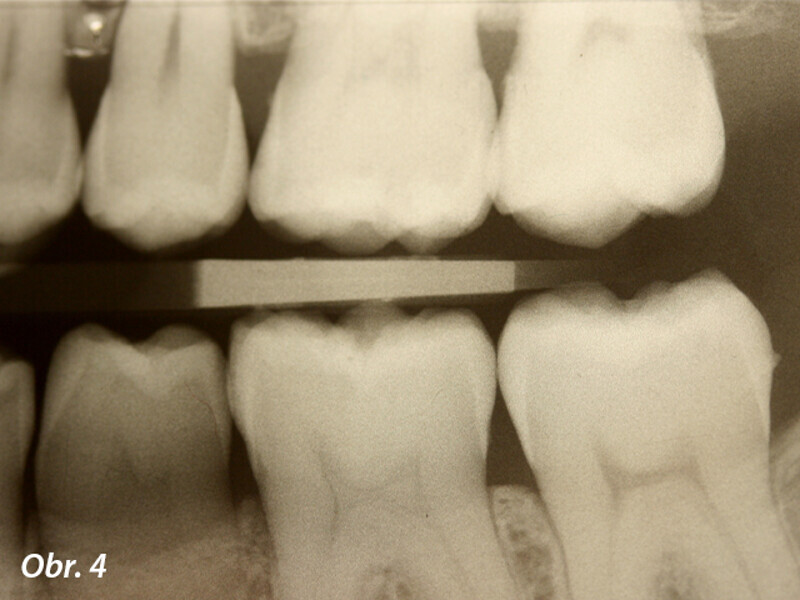

Funkční, anatomická a estetická harmonie s novým kompozitním materiálem Enamel Plus HRi